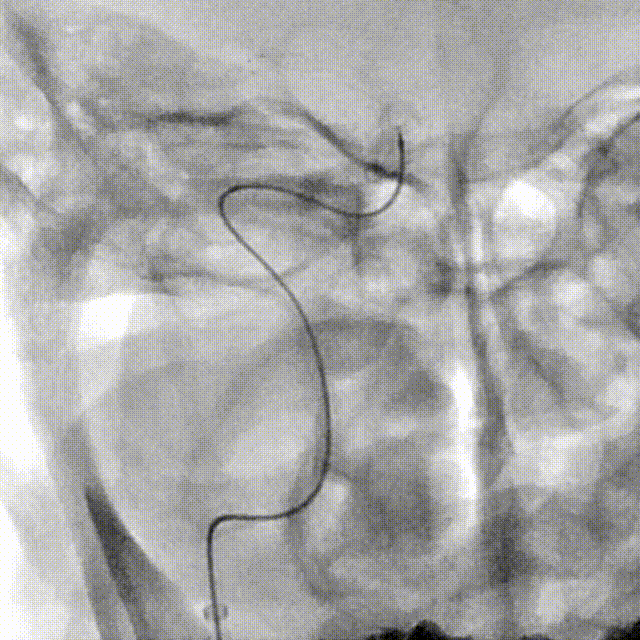

NeuroHawk Case 6